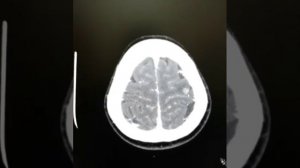

Четыре метастазы в головном мозге: алтайские нейрохирурги рассказали об особенностях своей профессии